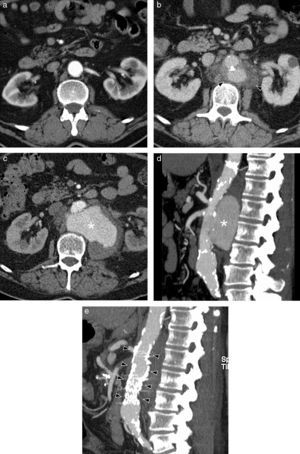

Takayasu's Arteritis of a 41-year-old woman with intestinal angor and right leg claudication. (a) CT study with contrast. Irregular-looking thoracoabdominal aorta with wall thickening (arrow heads). (b) MIP image of angio-MR showing stenosis in the ostium of both renal arteries (arrow heads) and in the primitive iliac arteries. (c) Angiographic correlation of the MR image findings. (d) Selective arteriography of the celiac trunk showing critical stenosis (arrow head) of 90% in the proximal portion thereof without distal affectation. (e) Successful implantation of Herculink low-profile expansible balloon endoprosthesis (arrow head) (of 7×18mm).

Takayasu's arteritis of a 34-year-old woman. (a) Axial CT image with contrast showing dilation and significant calcification of the ascending and descending thoracic aorta (arrow heads). (b) Axial CT cut with contrast. Abdominal aorta and upper mesenteric ostial artery wall thickening (arrow head). (c) MPR sagittal reconstruction. Parietal irregularity (arrow heads) and extensive calcification of the aorta. (d) Coronal MIP reconstruction of angio-MR of supraaortic trunks. Complete occlusion of both subclavian arteries in their prevertebral portions (black arrow heads) with posterior recannulation on the left side by cervical arteries (white arrow heads) and on the right side by the vertebral artery (arrow).

MR is very useful to detect precocious changes in the aortic wall and it is the technique of choice to follow up the disease's evolution, especially in young patients for whom it avoids radiation.4,5 Enhanced sequences on T1 are used with fat saturation and contrast to show the tardive enhancement of the wall, which has been related with the disease's activity (Fig. 1b),7–10 although Isobe, in a recent study of 150 patients, disagrees with the clinical meaning of this finding that is observed in patients both with and without an active disease.11 A hyperintensity of the sequences enhanced on T2 is indicative of wall edema. Like CT, MR allows to identify wall thickening, stenosis (Figs. 3b and 4d), thrombi and aneurysms. In addition, it may prove thickening of the aortic valves and pericardial affectation.4

Treatment of the acute phase is based on glucocorticoids and immunosuppressors. Treatment of vascular stenosis is the surgical bypass or endovascular intervention in critical stenosis (Fig. 3c–e).6